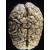

Alcuni ricercatori della Scuola di Medicina dell'Università di Yale hanno identificato un gene sul cromosoma umano 6, chiamato DCDC2, che sarebbe associato alla dislessia, un disturbo della lettura che colpisce milioni di bambini e di adulti. Gli scienziati hanno scoperto che una mutazione genetica di DCDC2 conduce a un difetto nella formazione dei circuiti cerebrali che rendono possibile la lettura. L'alterazione genetica sarebbe ereditaria.

I ricercatori hanno usato un approccio statistico per studiare e confrontare marcatori specifici del DNA in 153 famiglie dislessiche. "Ora - spiega Gruen - abbiano forti prove statistiche del fatto che un gran numero di casi di dislessia, forse il 20 per cento, è dovuto al gene DCDC2. L'alterazione genetica su questo cromosoma corrisponde alla cancellazione di una regione regolatrice. Lo stesso gene è espresso nei centri della lettura del cervello, dove modula la migrazione di neuroni. Questa architettura cerebrale è necessaria per leggere normalmente".